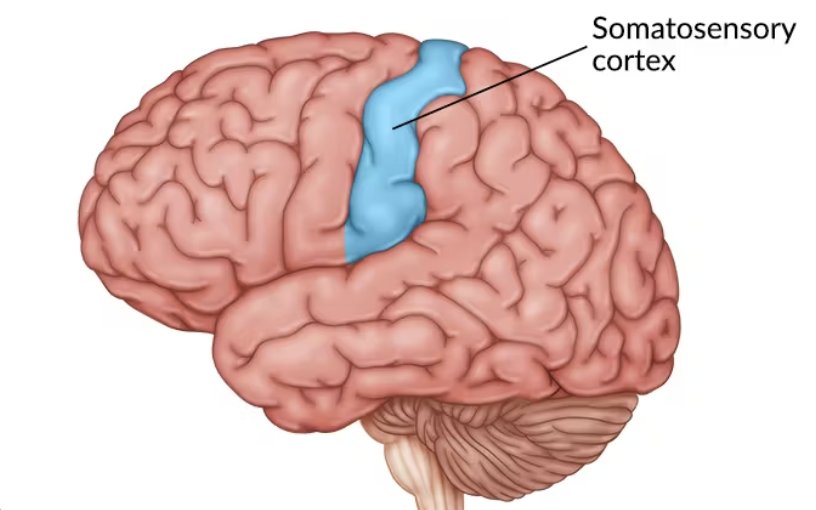

Lobe function: Somatosensory cortex(sense processing), Sensory integration, Spatial awareness

Parietal Lobe

Which cortex senses the stimulus immediately (pain, temperature, feels)?

Primary Somatosensory Cortex